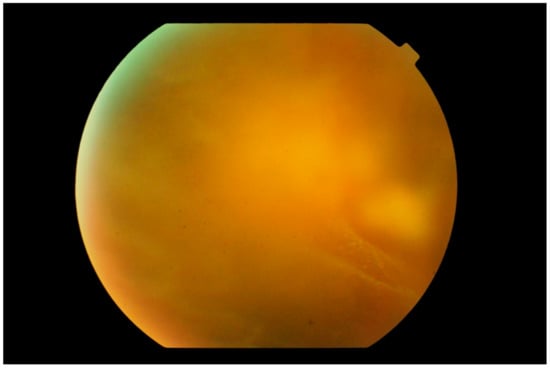

3. Clinical Features

Differential Diagnosis